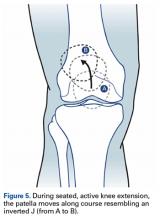

Beyond walking and standing, additional functional tests (eg, single-leg squat, single-leg balancing, step-down test) were suggested as reliably provoking these pathologic kinematics.30 It is also suggested that the patient be examined sitting with lower legs hanging. In many cases, patients who are asked to actively extend the leg with LPD present a so-called J sign, which means the patella moves laterally close to terminal knee extension (Figure 5). Examination continues with the patient supine. The physician uses the patella glide test to determine how far the patella can be translated toward lateral and medial. Grade 1 indicates the patella can be translated one-fourth of its width, and grade 4 indicates it can be translated its full width31 (Figure 6).